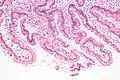

Under microscopy, the duodenum has a villous mucosa. This is distinct from the mucosa of the pylorus, which directly joins to the duodenum. Like other structures of the gastrointestinal tract, the duodenum has a mucosa, submucosa, muscularis externa, and adventitia. Glands line the duodenum, known as Brunner's glands, which secrete mucus and bicarbonate in order to neutralise stomach acids. These are distinct glands not found in the ileum or jejunum, the other parts of the small intestine.[10]: 274–275

The villi of the duodenum have a leafy-looking appearance, which is a histologically identifiable structure. Brunner's glands, which secrete mucus, are only found in the duodenum. The duodenum wall consists of a very thin layer of cells that form the muscularis mucosae.